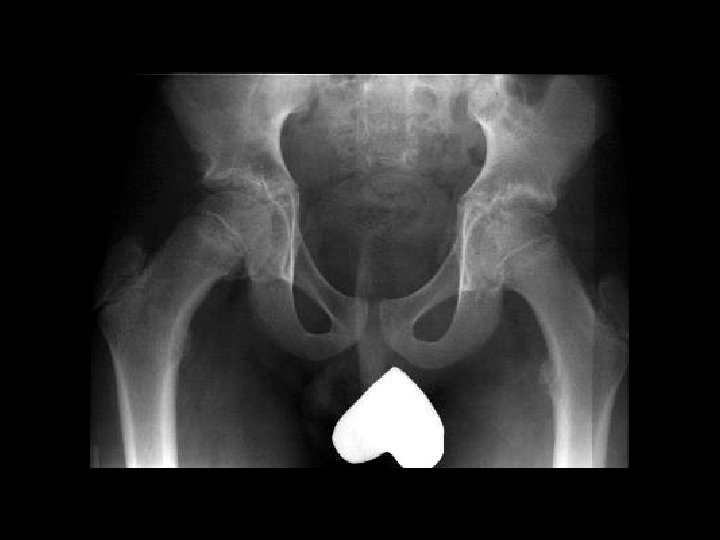

Femoral Head AVN • Findings: – bilateral femoral head AVN w/o collapse – right pelvic renal tx • Ddx: – Pancreatitis – Sickle Cell Dz – Caison’s Dz – etc…